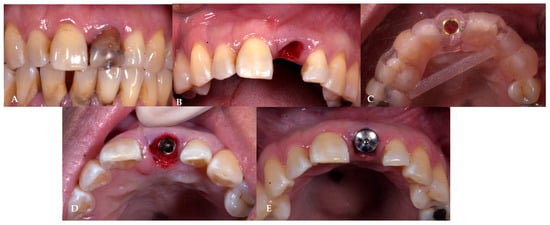

2.7. Case Presentation